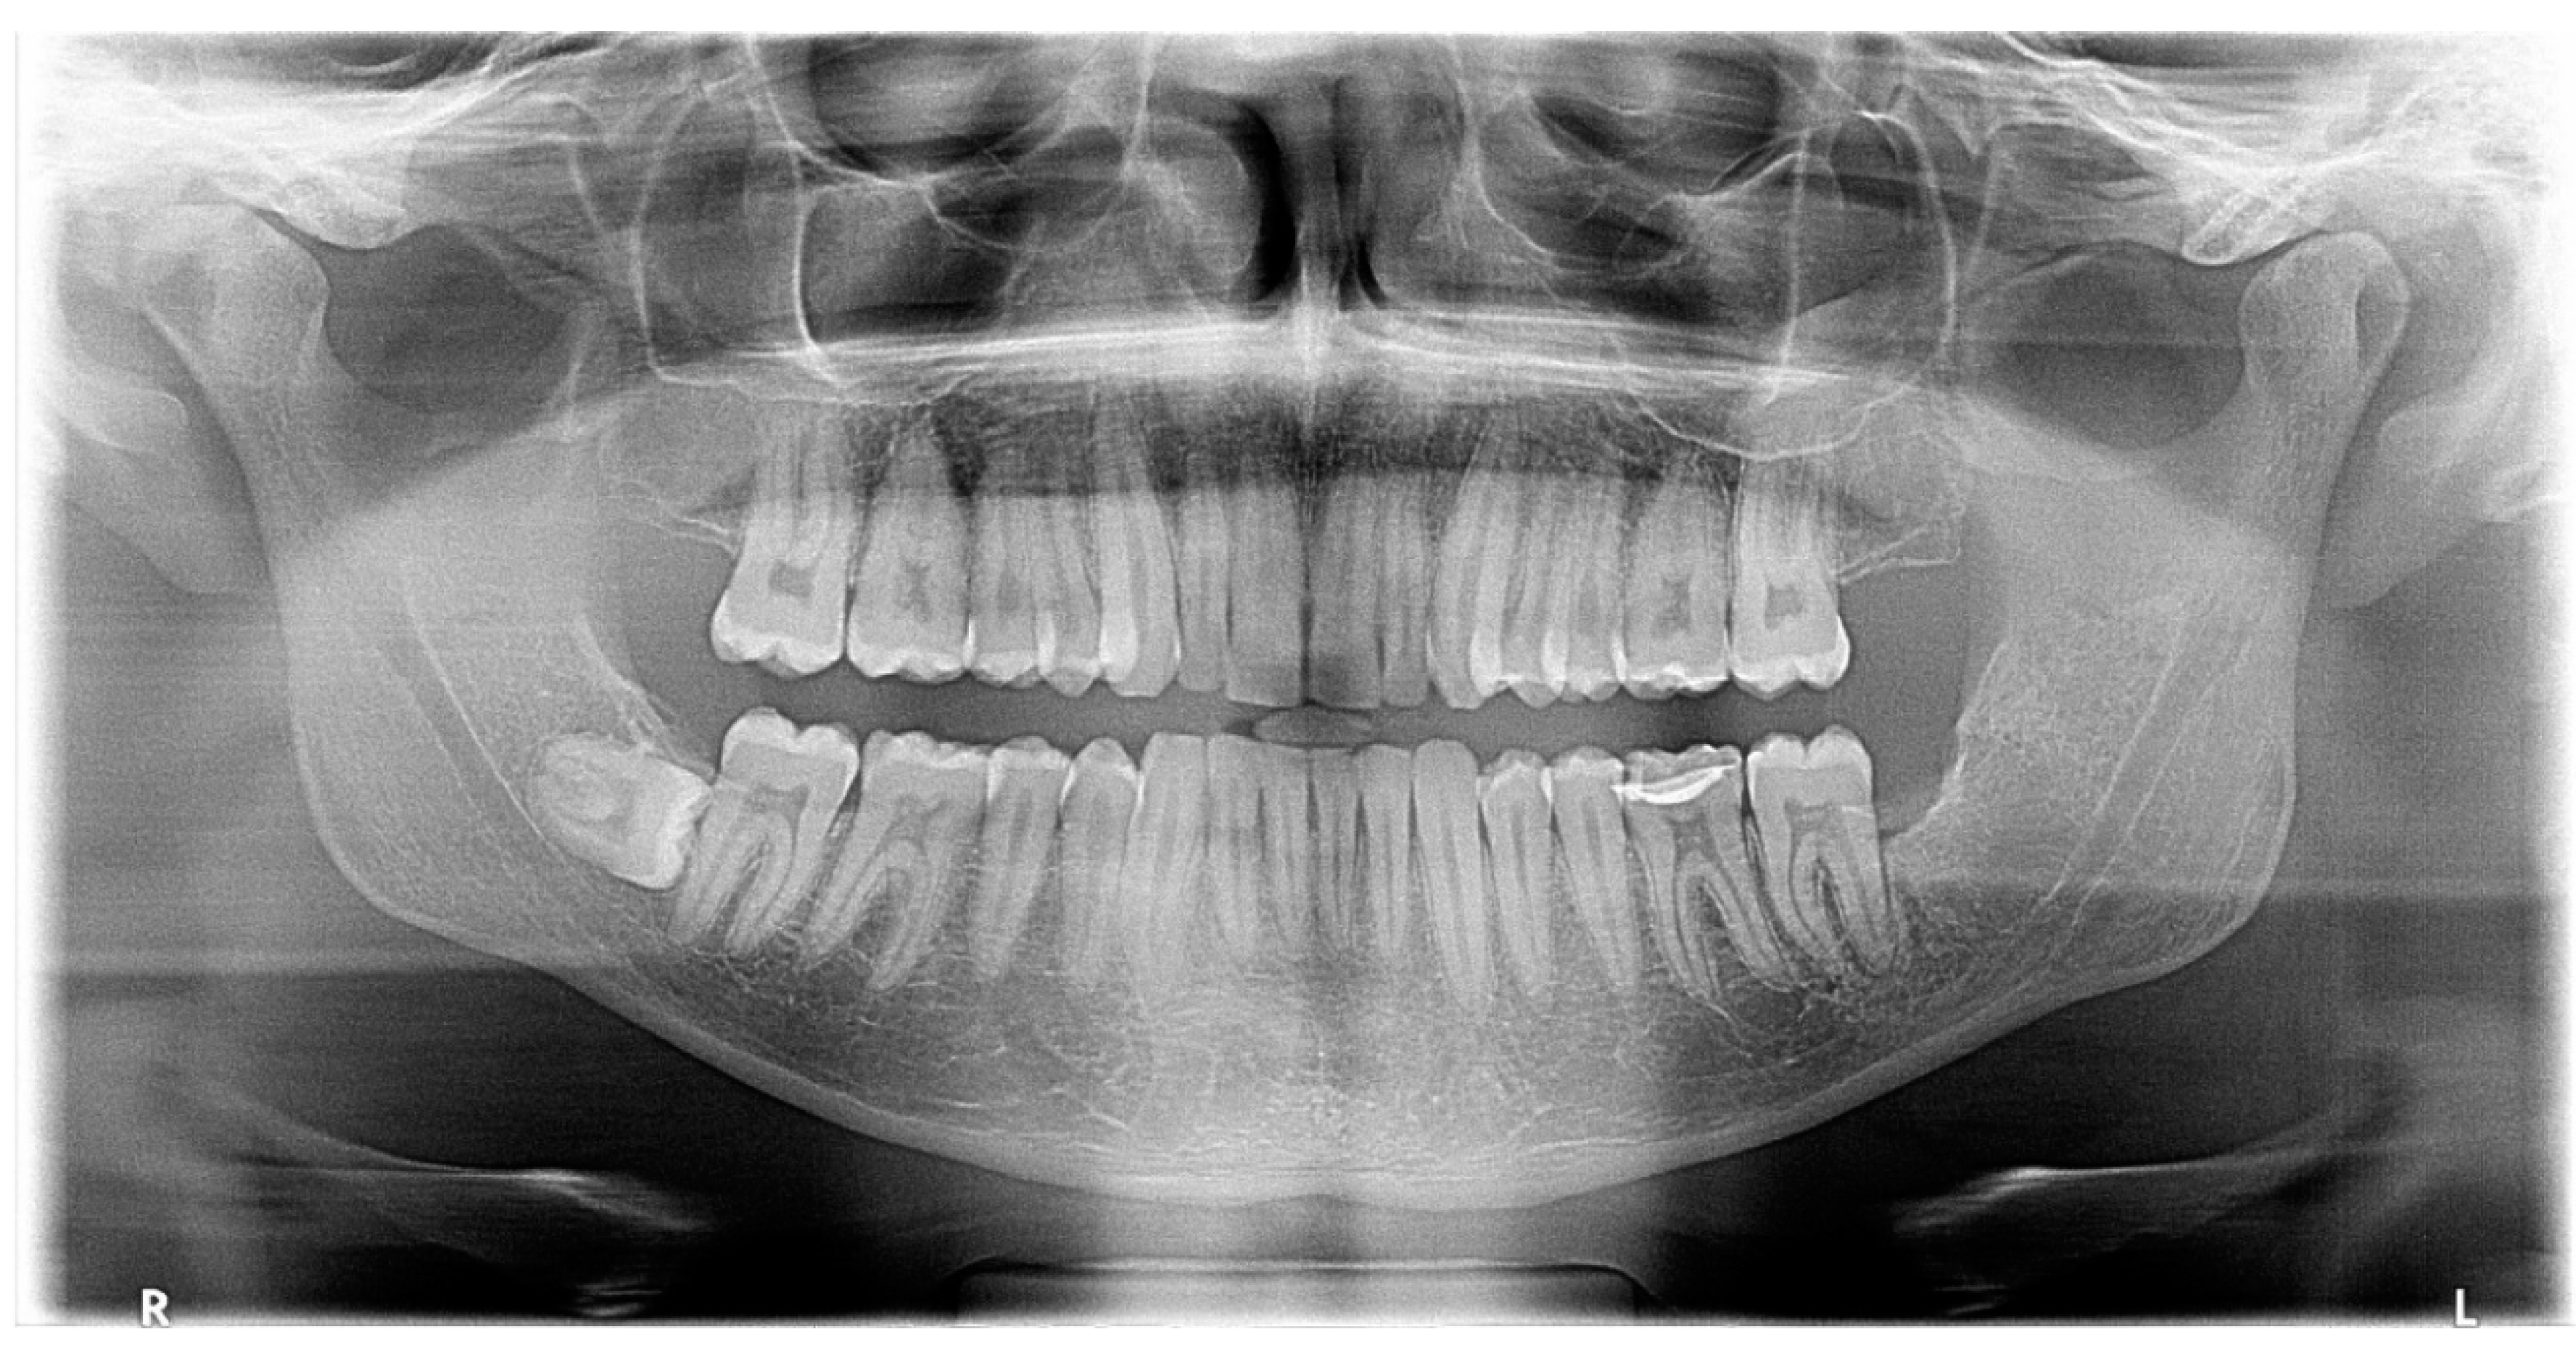

Panoramic radiography revealed the presence of a pericoronal radiolucent lesion around the crown of an impacted tooth #38 (horizontally positioned with mesial orientation) (Figure 1). The lesion measuring 27 × 22 mm was well defined and unilocular, surrounded by a thin sclerotic bone. It overlapped with the distal root of tooth #37, causing adjacent bone resorption but with no signs of root resorption. The cyst seemed to interfere with the inferior alveolar canal (IAC), which appeared displaced caudally by the lesion. A presumptive diagnosis of CD was made.

Figure 1.

Panoramic X-ray of case #1.